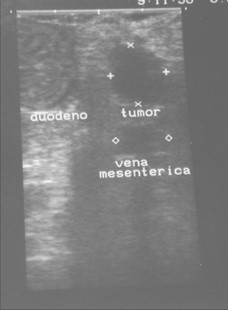

Paciente masculino de 35 años de edad, con antecedentes de tabaquismo, etilismo, consumo de sustancias psicoactivas. Ingresa al hospital de Sanatorio Franchin el 24 de mayo de 2024, donde se constata hipoglucemia severa con buena respuesta al glucosado hipertónico endovenoso. Al examen físico con la típica tríada de Whipple, dado por síntomas neuroglucopénicos de alteración del estado de conciencia, glucemia de 25 mg/dl y alivio sintomático después de la administración de glucosa. El paciente recupera el estado de conciencia y refiere dolor abdominal a nivel de epigastrio, por lo que se le realiza ecografía abdominal, donde se evidencia lesión nodular hipoecogénica en cuerpo del páncreas. Por esta razón se pasa al paciente a tomografía, donde se constata una formación nodular a nivel del cuerpo del páncreas, que presenta un ávido realce en fase arterial con homogeneización de la lesión en tiempo tardío.

Una vez que tengamos una fuerte sospecha diagnóstica basada en la clínica y el laboratorio bioquímico viene la localización del tumor, que se puede realizar a través de métodos no invasivos, como la ecografía, que como método de abordaje inicial no está mal para una primera exploración, pero debemos conocer que su sensibilidad es muy baja, del 9%. Pero como un estudio no invasivo, rápido, relativamente económico, y si está disponible en nuestro servicio, se puede utilizar. Los insulinomas se pueden observar por este método como una imagen nodular hipoecogénica que puede mostrar ante la presencia de Doppler color un patrón periférico o centrípeto, porque recordemos que estos son tumores hipervasculares, lo que significa que tienen una alta densidad de vasos sanguíneos.

Para mi caso, y dando una visión general de los métodos de imagen no invasivos en esta revisión retrospectiva, solo a uno de los pacientes se le detectó la lesión por ecografía, donde se visualizó una lesión nodular hipoecogénica en el cuerpo del páncreas. A los demás pacientes se les detectó la lesión por tomografía en estudio trifásico, donde resaltan las características ya descritas por la literatura de lesiones hipervasculares con intenso realce en fase arterial, localizadas en diferentes partes del páncreas, como cabeza, cuerpo y cola.